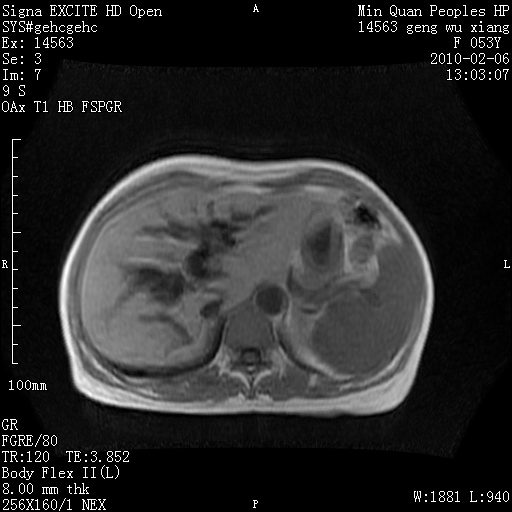

标题: MRI2762:胆道梗阻原因?

f,53y,全身黄染多日。

高位胆道梗阻 胆管癌可能性大

支持 高位胆道梗阻 胆管癌可能性大。